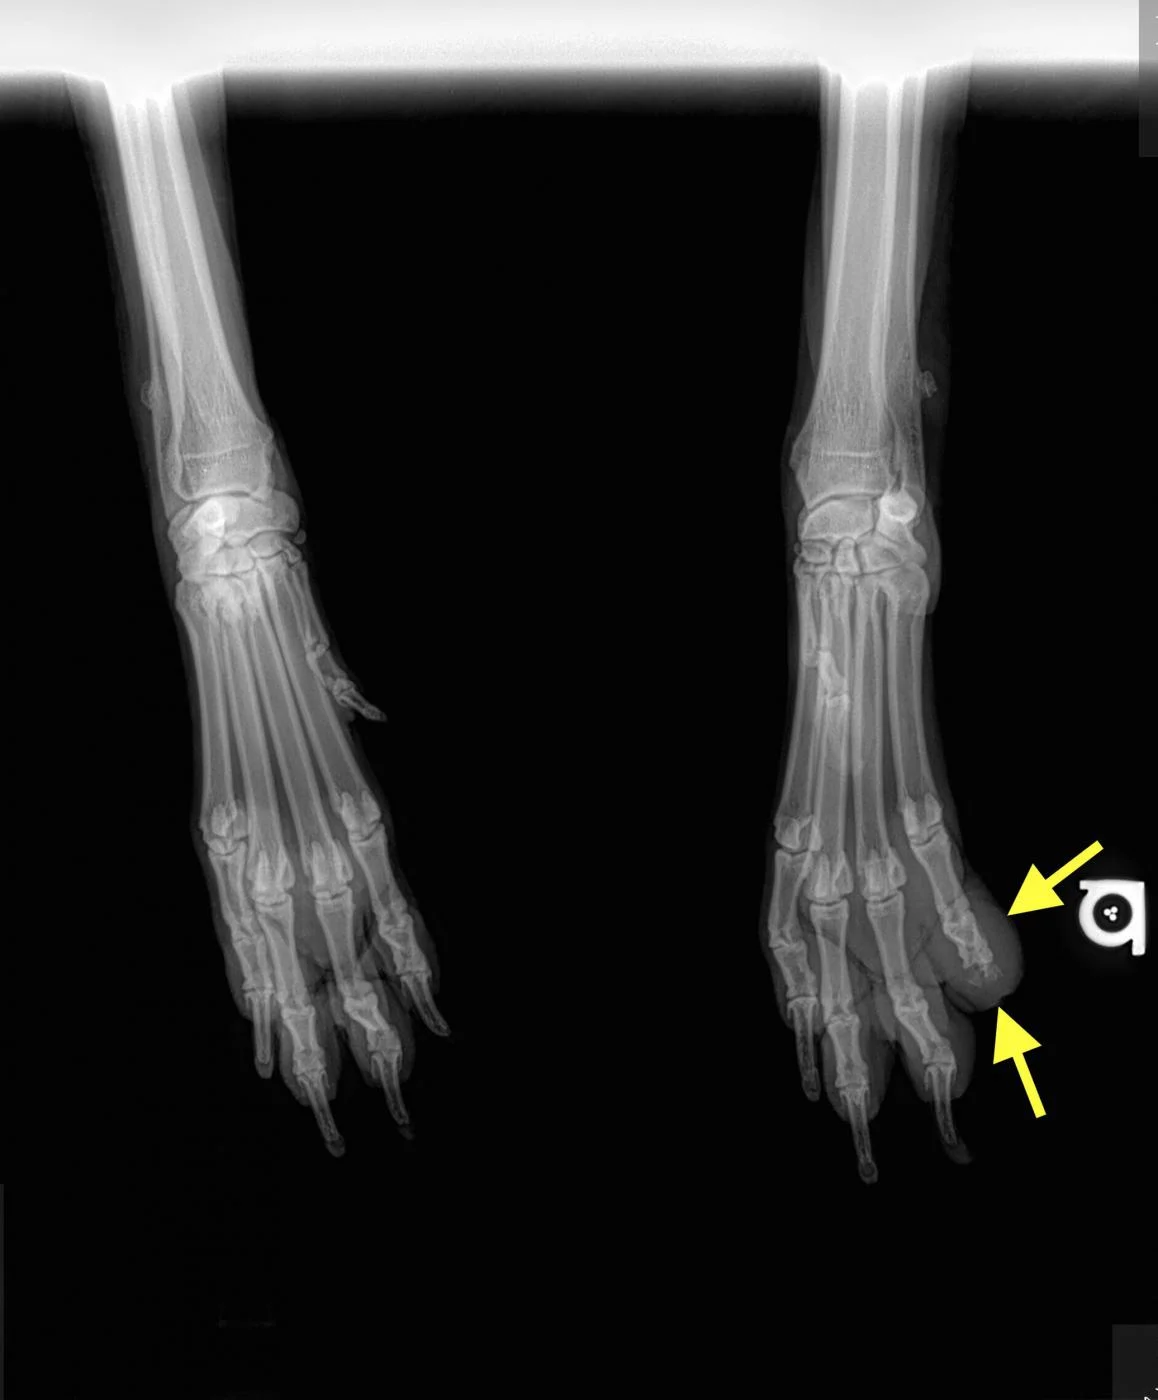

Digit melanoma

A single craniocaudal radiograph illustrates the forepaws of a 12-year-old neutered male Airedale terrier with digit melanoma. Moderate circumferential soft tissue swelling of the 5th digit of the left thoracic limb and significant lysis of the distal phalanx can be noted (arrows). The aggressive monostotic lesion of the distal phalanx of the 5th digit and associated soft tissue swelling are consistent with digital melanoma, which was confirmed via histopathology after digit amputation.